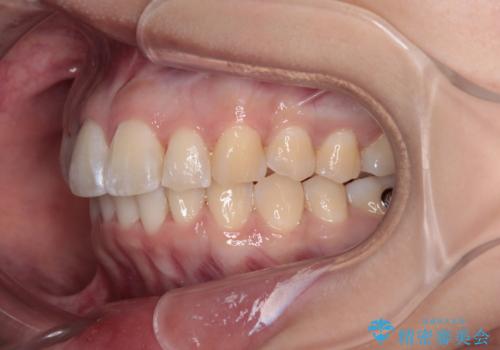

- 前方に主張した前歯2本を気にして来院された患者様です。

下顎前歯がデコボコしており、その影響で上顎前歯が前方に押し出されている状態でした。

口元が閉じにくいという印象はなかったため、非抜歯矯正にて歯列を整えていくこととしました。

上下左右の親知らずを抜歯し、上下ともに歯列を後方と側方に拡大し、口元を突出させることなくデコボコを解消することとしました。

前歯の形が台形であり、歯列が整ったところでブラックトライアングルが目立つ仕上がりとなったため、IPR(歯と歯の間を削る処置)によって歯の形態を修正し、隙間の目立たない歯列に仕上げることができました。